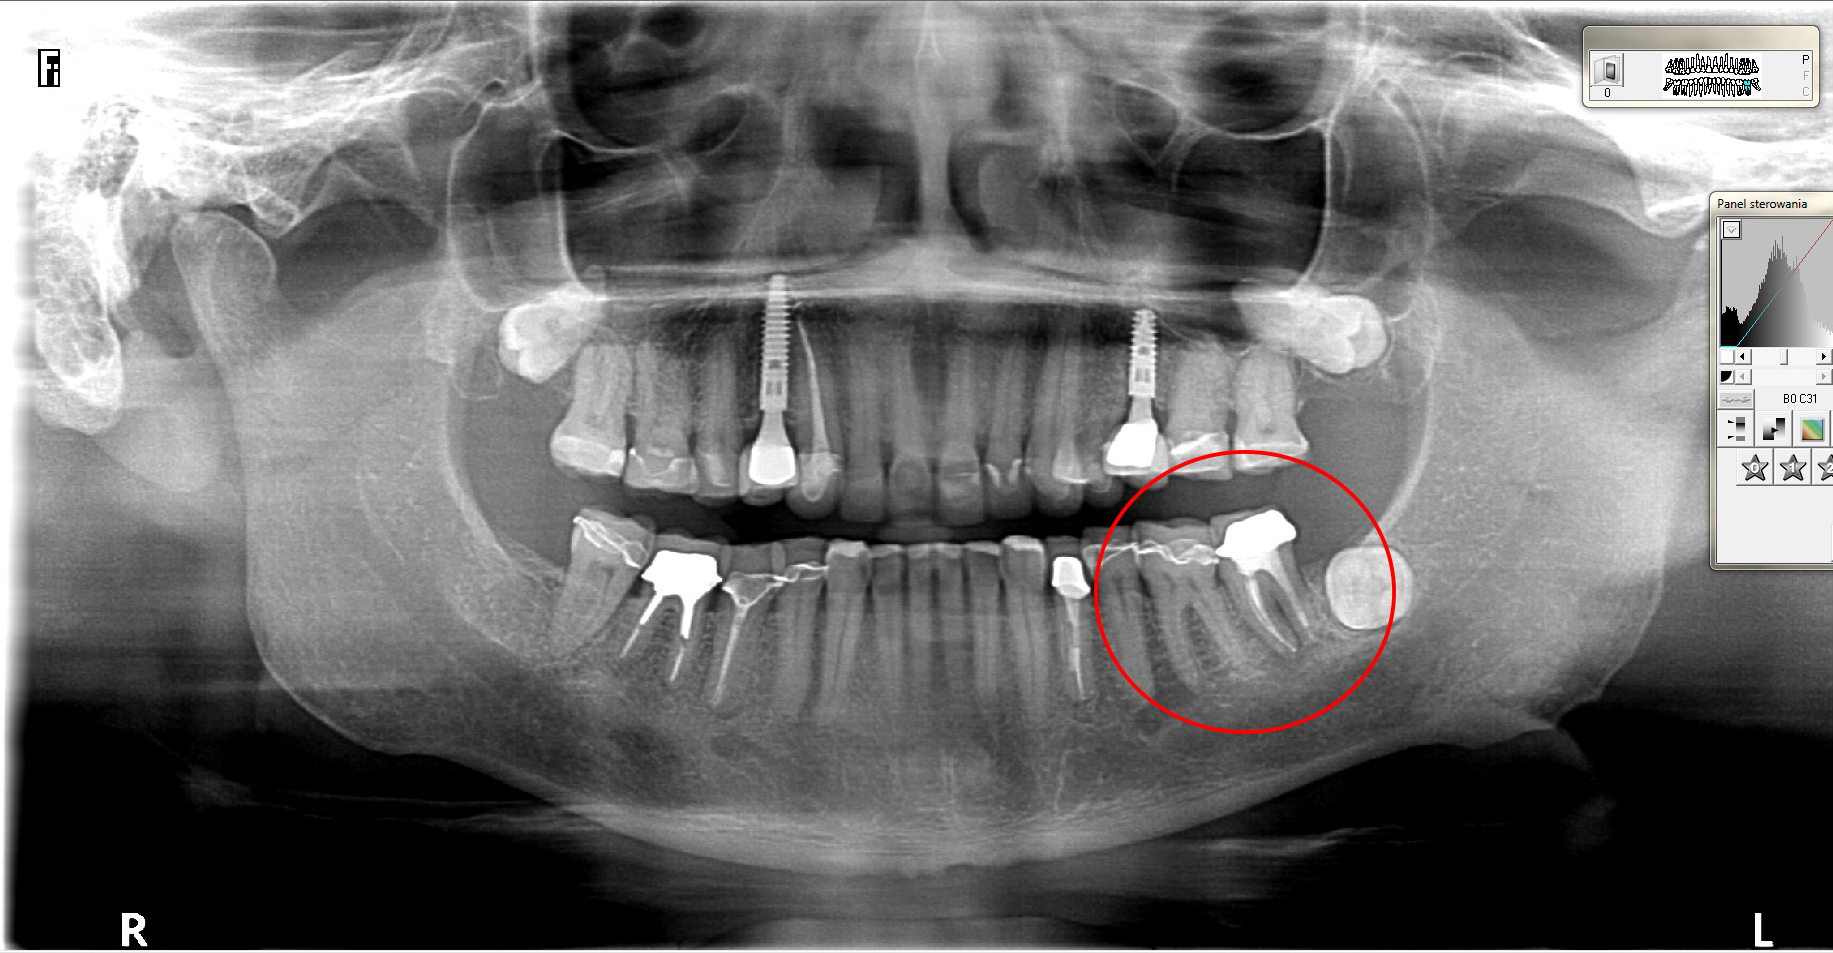

Ten problem najczęściej dotyczy zębów trzonowych żuchwy oraz górnych przedtrzonowców. Może również towarzyszyć wadom zgryzu, w zębach zniszczonych przez erozję, abrazję lub atrycję. Pionowe złamanie korzenia jest trudne do zdiagnozowania. Zdjęcia RTG nie zawsze bowiem ukaże „całą prawdę”. Coraz powszechniej używane obrazowanie CBCT (3D) pomaga w postawieniu diagnozy pionowego złamania zęba lub korzenia.

Do pionowego złamania korzenia zęba może dojść podczas zabiegu leczenia kanałowego poprzez używanie zbyt dużej siły w czasie wypełniania lub oczyszczania kanału. Może być również spowodowane zaklinowaniem się narzędzia w kanale. Pionowe korzenia zęba zawsze prowadzi do usunięcia całego zęba. Dbałość o profilaktykę i terminowe zgłaszania się do gabinetu stomatologicznego z towarzyszącą diagnostyką rentgenowską znaczącą redukuje te ryzyka.

Nadzieją na przywrócenie funkcji żucia w zakresie utraconego zęba jest oczywiście – implant. Dynamiczny rozwój implantologii pozwala na uzupełnienie braków zębowych szybko, przewidywalnie i bezboleśnie.